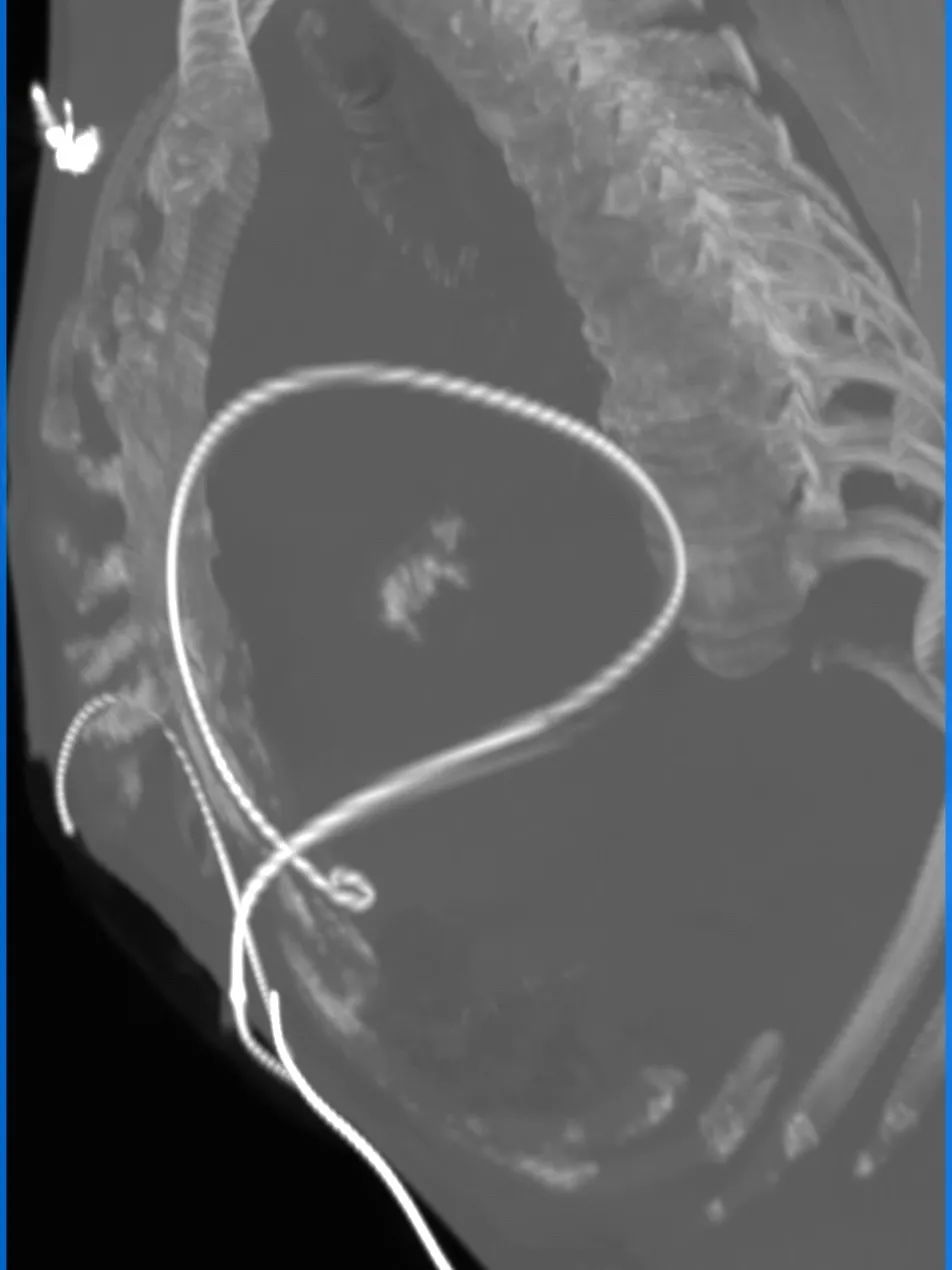

26VenusAplus+snare

瓣膜内22mm球囊后扩张,左冠无显影

LM烟囱支架植入4.0*30mm